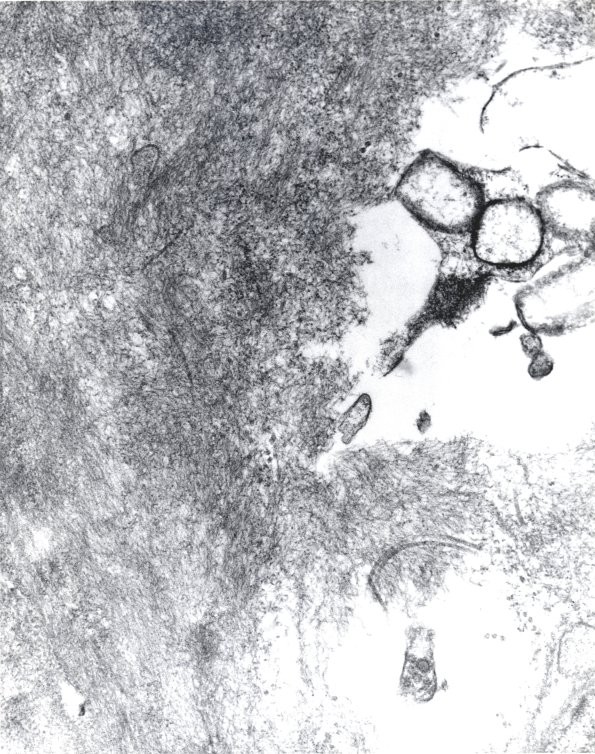

Asymmetric distribution of vascular amyloid seen at several magnifications. (electron micrographs)